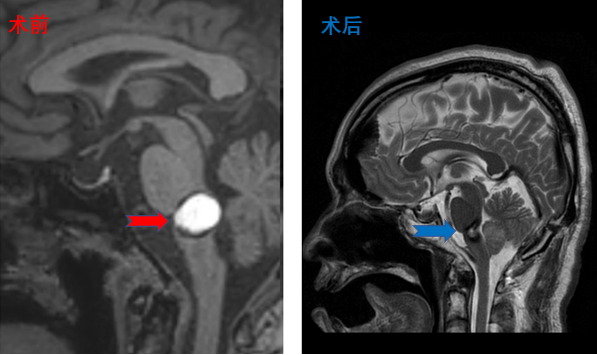

颅咽管瘤患者影像,患者术后视力明显改善,无明显尿崩及电解质紊乱